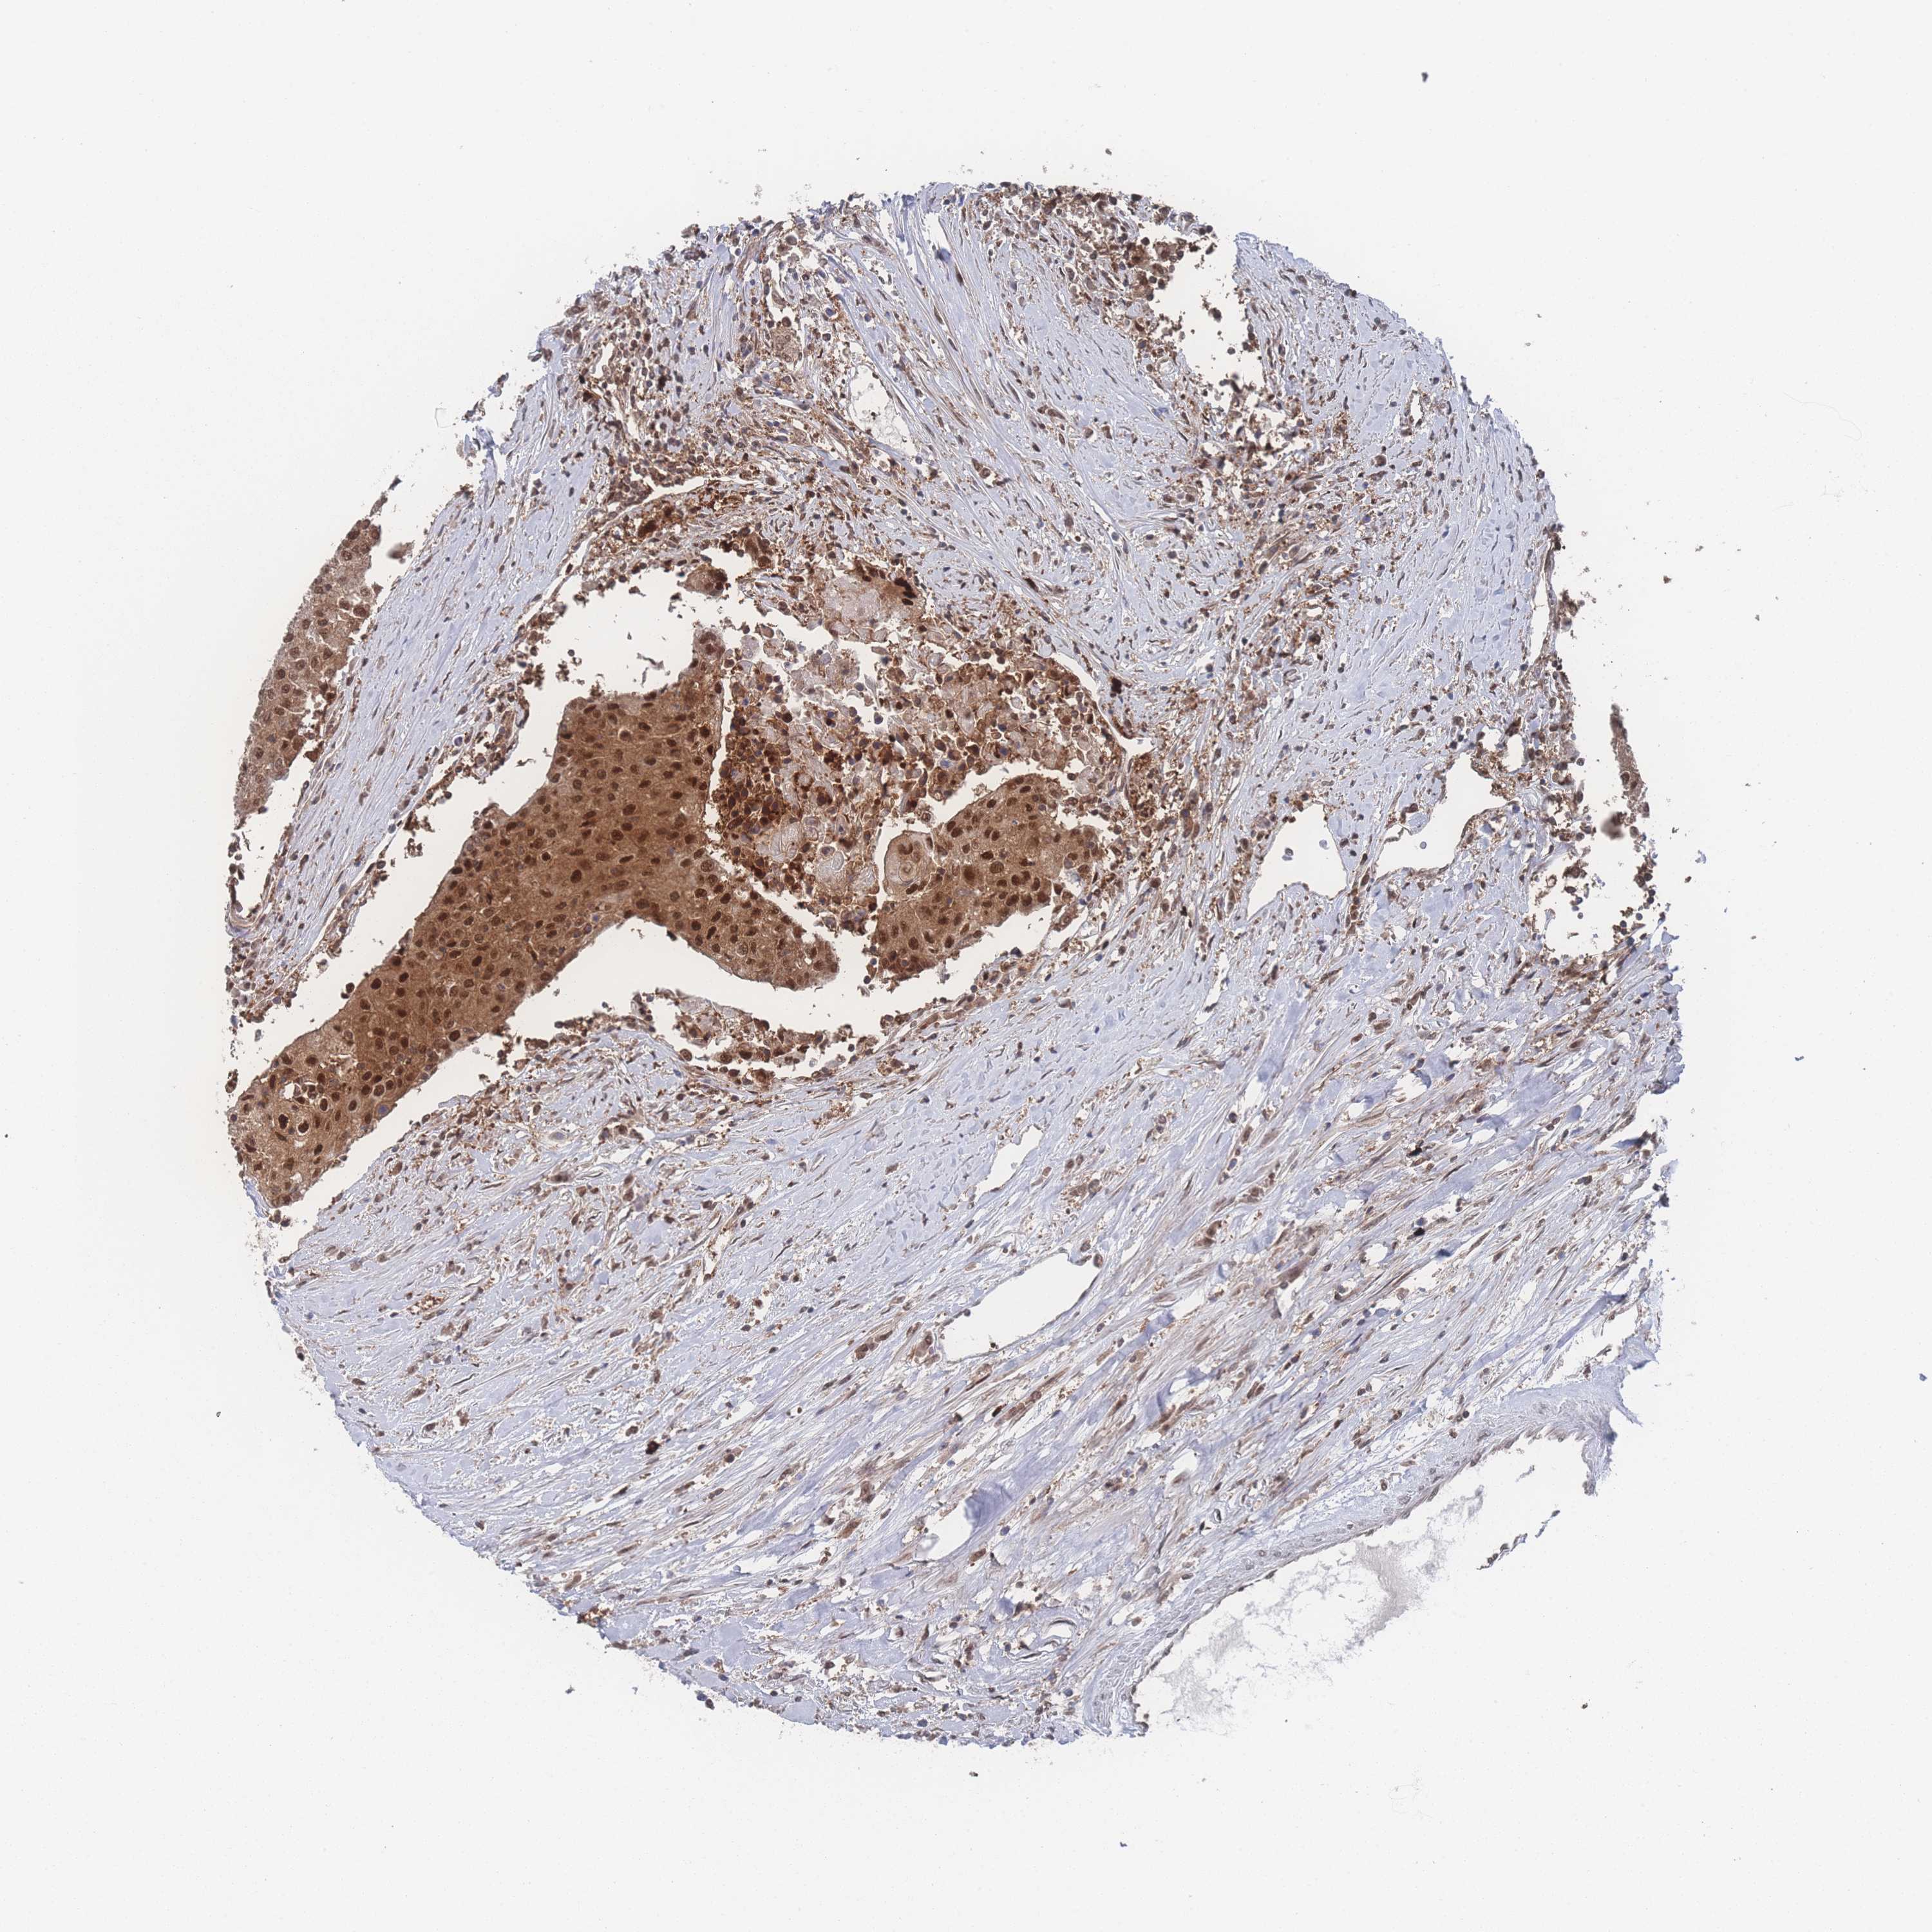

UROTHELIAL CANCER - Protein expressioni

A mouse-over function shows sample information and annotation data. Click on an image to view it in a full screen mode. Samples can be filtered based on level of antibody staining by selecting one or several of the following categories: high, medium, low and not detected. The assay and annotation is described here.

Note that samples used for immunohistochemistry by the Human Protein Atlas do not correspond to samples in the TCGA dataset.

Antibody stainingi

Antibody staining in the annotated cell types in the current human tissue is reported as not detected, low, medium, or high, based on conventional immunohistochemistry profiling in selected tissues. This score is based on the combination of the staining intensity and fraction of stained cells.

Each image is clickable and will lead to virtual microscopy that enables deeper exploration of all samples and also displays staining intensity scores, fraction scores and subcellular localization as well as patient and tissue information for each sample.

Antibody HPA037646

Antibody HPA043891

Antibody CAB033765

Antibody CAB079995

Staining

High

Medium

Low

Not detected

Intensity

Strong

Moderate

Weak

Negative

Quantity

>75%

75%-25%

<25%

None

Location

Nuclear

Cytoplasmic/membranous

Cytoplasmic/membranous,nuclear

Urothelial carcinoma, High grade

Urothelial carcinoma, Low grade

Urothelial carcinoma, NOS